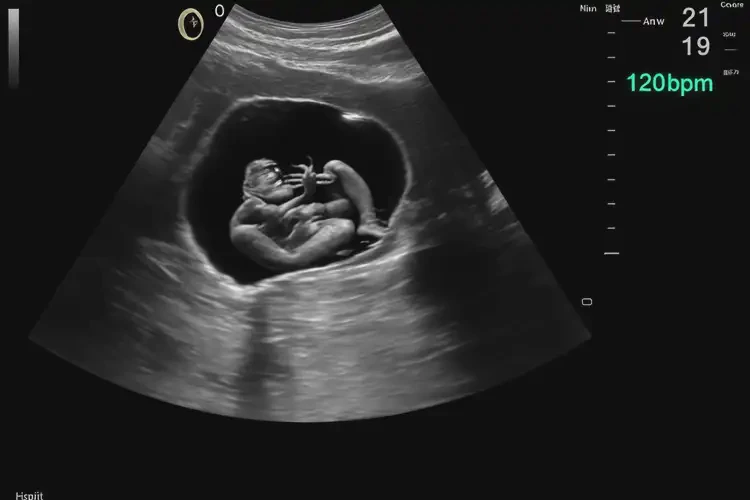

孕21周6天胎心175還要保胎嗎(圖1)

孕21周6天胎心175還要保胎嗎

胎心率175次/分鐘在孕21周6天時可能偏高,但是否需要保胎需綜合評估。

胎心率是評估胎兒健康的重要指標之一。正常情況下,孕20-24周的胎兒平均胎心率應在120-160次/分鐘之間。胎心率會受到多種因素的影響,包括胎兒活動、孕婦情緒和身體狀況等。單次胎心率測量結果并不能完全反映胎兒的健康狀況。